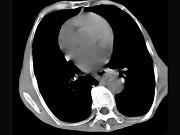

问题 女,71岁,进食时有梗阻感,进行性加重半年,影像检查如图,最可能的诊断是()

选项 A.贲门失弛缓症 B.食道癌并纵隔淋巴结转移 C.食道良性狭窄 D.返流性食道炎 E.食道静脉曲张

答案 B